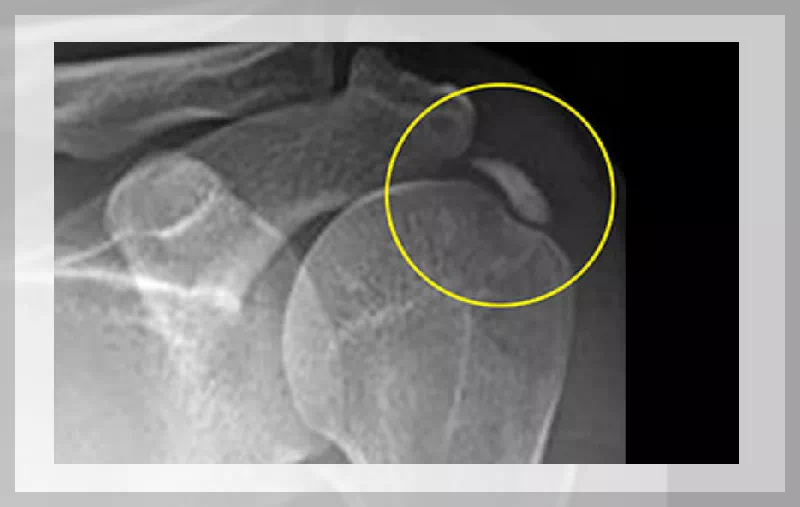

어깨 부위 힘줄염의 주요 증상으로는 어깨 통증, 움직임 제한, 근력 감소 등이 있습니다. 특히 어깨를 움직일 때 통증이 심해지며, 밤에 통증이 심해지는 경우도 많습니다. 이러한 증상은 일상 생활에 큰 불편을 초래할 수 있습니다.

어깨 부위 힘줄염이 있을 경우, 어깨를 움직일 때마다 통증이 느껴집니다. 통증은 가벼운 통증에서부터 심한 통증까지 다양하게 나타날 수 있으며, 특히 팔을 들어올리거나 뒤로 젖힐 때 더욱 심해집니다.

어깨 힘줄염은 어깨의 움직임을 제한시킵니다. 이는 염증으로 인해 힘줄이 부어오르거나, 통증 때문에 어깨를 자유롭게 움직이기 어려워지기 때문입니다. 결과적으로 일상적인 활동에 많은 제약을 받게 됩니다.